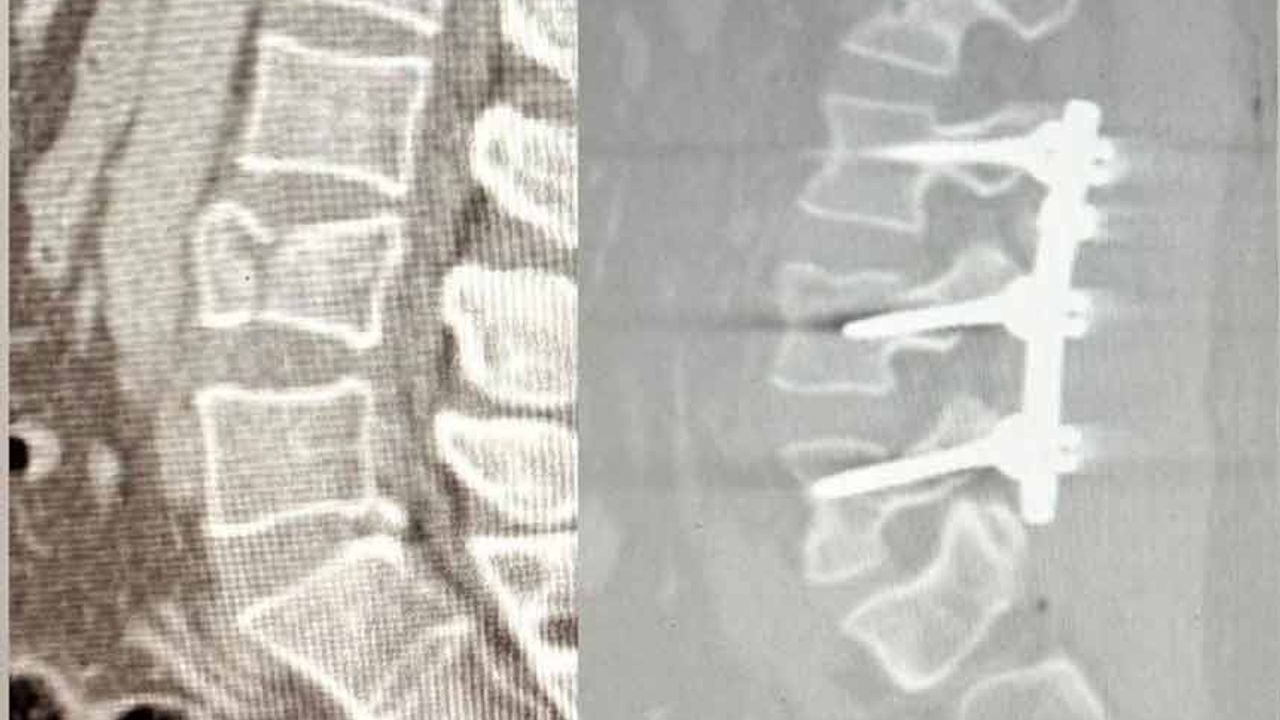

Yapılan tetkiklerde omurgada çökme kırığı tespit edilmesi üzerine hasta, ortopedi uzmanları Op. Dr. Muhammed Serpi ve Op. Dr. Mustafa İçen tarafından ameliyata alındı.

Ameliyat sırasında bel bölgesindeki omurların sabitlenmesini sağlayan lomber stabilizasyon tekniği kullanıldı. Hastane tarihinde ilk kez gerçekleştirilen bu operasyon sonrası hasta sağlıklı şekilde yürümeye başladı.